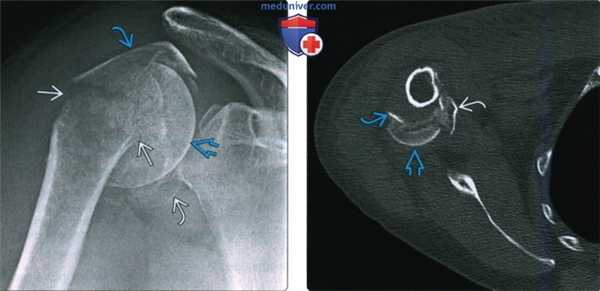

(Слева) На передне-задней рентгенограмме определяется перелом хирургической шейки плеча и переломы, включающие большой бугорок и малый бугорок. Переломы бугорков изолируют суставной отломок, что приводит к повышению риска а васкулярного некроза.

(Справа) На осевой КТ у этого же пациента визуализируются смещенные костные отломки в результате перелома головки плечевой кости и малого и большого бугорка. Поскольку произошло как смещение >1 см, так и отклонение >45° при всех трех видах переломов, это перелом из четырех сегментов.